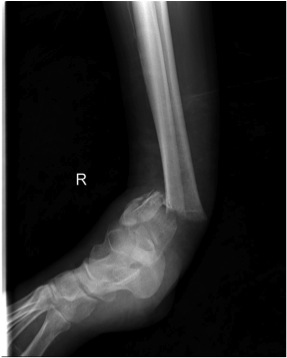

Temporary External fixation

Indications

- significant swelling

- significant displacement / non controlled in cast

- significant wounds, need for soft tissue coverage

Technique

- two pins proximal tibia

- trans-calcaneal pin

AO Trauma Ankle Bridging Delta Frame